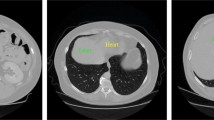

Multiphase computed tomography (CT) is widely used for the diagnosis of liver lesions. Accurate detection of lesions in multiphase CT images is important in the diagnosis of liver cancer. However, to detect liver lesion from multiphase CT images, the multiphase images must be registered accurately as a preprocessing step, which is complicated by liver deformation. Therefore, we herein propose an improved mask R-CNN (Region with Convolutional Neural Network), in which deformable convolution modules are used for feature extraction, unlike the use of conventional convolution modules in mask R-CNN. Experimental results show that the proposed method performs better compared to the baseline (i.e., the original Mask R-CNN with ResNet-50). In particular, our method yields an overall AP50 of 4.8. In terms of AP (Average Precision) and AP75, our method yields values that are 1.6 and 2.6 higher than those of the original mask R-CNN, respectively. Then in the mask AP, our method yields values that are 1.8, 3.2, and 1.1 higher than those of the original mask R-CNN, respectively.